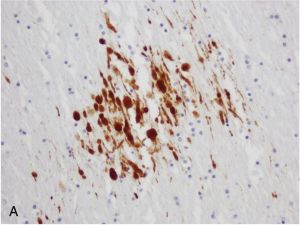

Neuroimaging techniques reveal the severity of TAI. Conventional imaging may not detect Grade 1 TAI, but Grades 2 and 3 may show visible hemorrhagic lesions in the corpus callosum and brainstem. Advanced techniques like immunocytochemical staining for amyloid precursor protein (APP) and neurofilament proteins help identify axonal damage more accurately.

TAI involves the rapid accumulation of axoplasmic components and organelles at the injury site, leading to axonal swelling and eventual disconnection. This process results in axonal retraction bulbs and may lead to the formation of neuritic plaques. The mechanical loading of the brain, especially in midline structures like the corpus callosum and brainstem, is influenced by anatomical features like the falx cerebri and tentorium cerebelli.